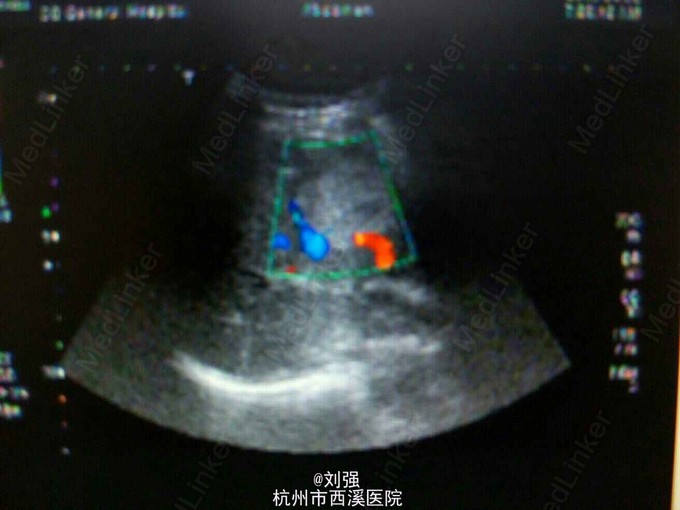

查体:生命体征平稳,心肺无特殊。腹部外形正常,腹式呼吸存在,无压痛以及反跳痛,肝区叩击痛阳性。辅助检查:实验室检查提示白蛋白下35.97g/L。腹部彩超提示:肝S5一大小为4.3cmX3.5cm实质性病灶,考虑血管瘤。腹部MRI检查提示S5段血管瘤。